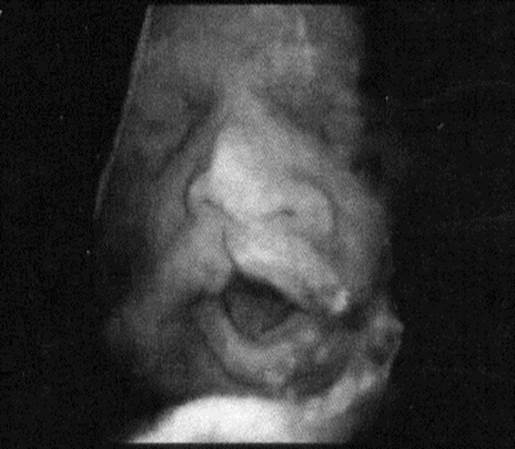

Больная С., 30 лет, обратилась к врачу женской консультации с жалобами на темно-кровянистые выделения из половых пу­тей накануне менструации, дисменорею, отсутствие беременности в течение 5 лет брака.

Из половых путей отходят кровянистые, темные, скудные выделения.

В л агалищное обследов а н и е: наружные половые органы развиты правильно. Влагалище — нерожавшей женщины. Шейка матки имеет субконическую форму, не деформирована. Наружный зев закрыт. Матка шаровидной формы, крупнее нормы, безболезненная при пальпации

Придатки не определяются. Зона их безболезненна.

Проведена гистерография. Данные гистерографии представлены на рисунке.

Ваш диагноз:

Гистерография:

+аденомиоз; //

киста яичников; //

рак матки; //

аномалия матки; //

миома матки.